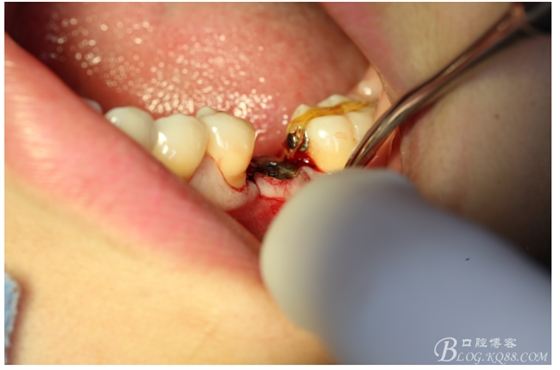

檢查:36.46缺失,36缺牙區(qū)近遠(yuǎn)中間隙約3mm,46缺牙區(qū)間隙約0.5mm,37.47.48近中傾斜,48近中面齲壞達(dá)牙本質(zhì)淺層,37牙周探診4mm,47近中探診深度5-6mm,不松,口內(nèi)照片及CT片如下:

口內(nèi)照片

處理:必蘭麻局部麻醉切開37遠(yuǎn)中牙齦,植入mini支抗釘一枚,37近中鄰面粘舌側(cè)扣,皮鏈輕力牽引,3周更換。